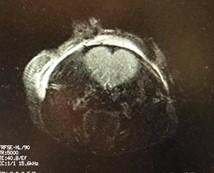

The love for MRI (A section of mouse brain)

The University of Ottawa Pre-clinical imaging core has been working with over 40 research groups over the past few years. We have helped researchers with acquiring high quality data for their numerous projects in cardiovascular and musculoskeletal systems, neuroscience, and other research areas. Our MRI and other imaging modalities provide a range of imaging options for small animal studies. The MRI provides high resolution images for studies involving stroke, joints, tumors, and many other conditions. If you are interested in using MRI (or other imaging modalities and their combination) for your study but you do not have the means to perform your experiment, we can now provide an end-to-end service. We offer a range of services including experiment design, documentation support, and imaging to data analysis. You tell us what you need, and we will make it happen. For more information contact Dr. Richard Aviv : raviv@toh.ca, the director of Pre-clinical imaging core.